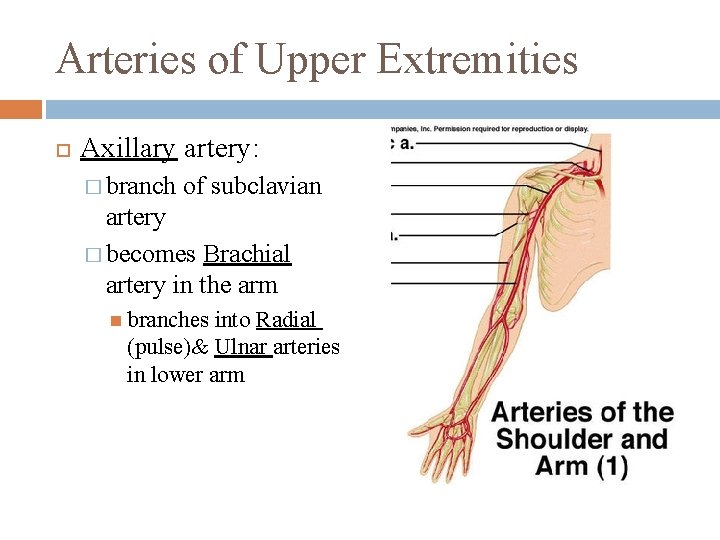

Arteries of Upper Extremities Axillary artery: � branch of subclavian artery � becomes Brachial artery in the arm branches into Radial (pulse)& Ulnar arteries in lower arm